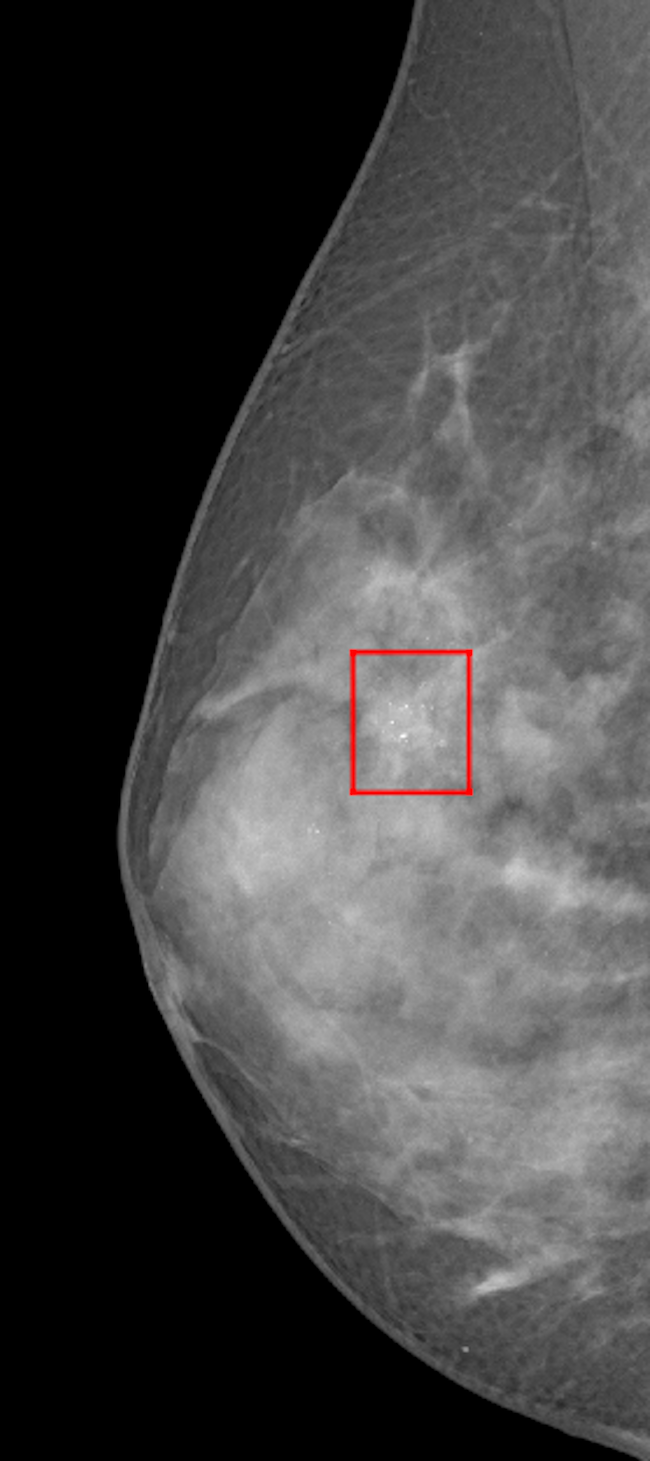

Once that the image has been patched, the Detector classifies each of these NxN input with a binary label relating to the potential presence of MCs inside. Candidate ROIs are subsequently segmented by Segmentator CNN, which brings to the creation of a binary mask of MCs (Figure 1).

An example of input region segmentated by the model is represented in Figure 1.